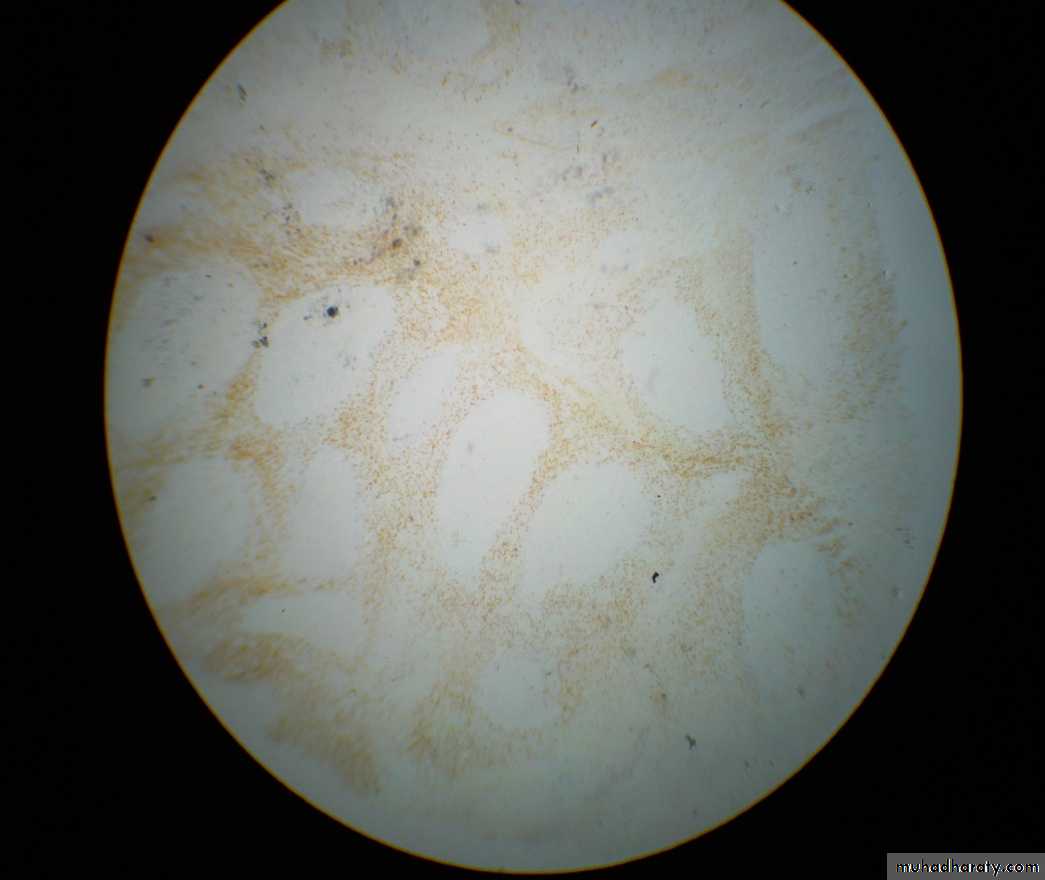

T cell markers: CD3 or CD4

1ry follicles : Few cells are positive

2ry follicles:M.Z: Few cells are positive

G.C: Few cells are positive

- IFA : Majority of cells are positive (2/3 of the cell population)

CD3 can not be differentiated from CD4 from this slideT cell markers: CD8

1ry follicles : Few cells are positive2ry follicles:

M.Z: Few cells are positiveG.C: Few cells are positive

- IFA : Minority of cells are positive (1/3 of the cell population)